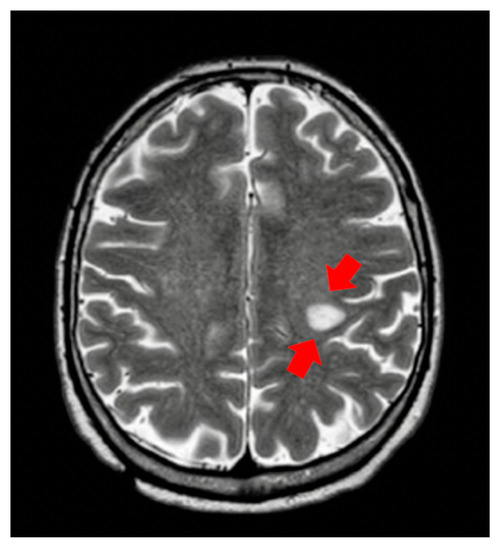

Encephalic Leukocytoclastic Vasculitis during Treatment with Sunitinib for Renal Cell Carcinoma: A Case Report

2. Cases and Methods